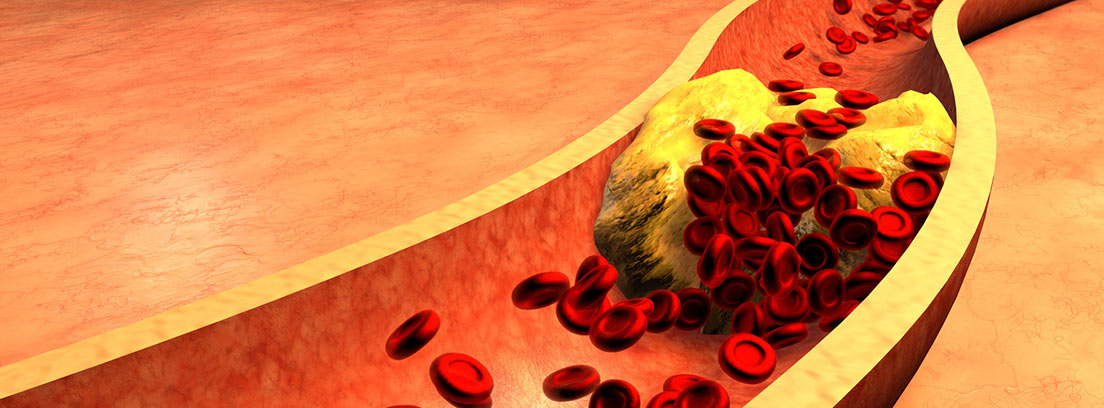

Las várices son venas dilatadas y tortuosas que aparecen principalmente en las piernas debido a una alteración en la circulación sanguínea. No solo representan un problema estético, sino que también pueden provocar dolor, cansancio, hinchazón y complicaciones venosas si no se tratan a tiempo.